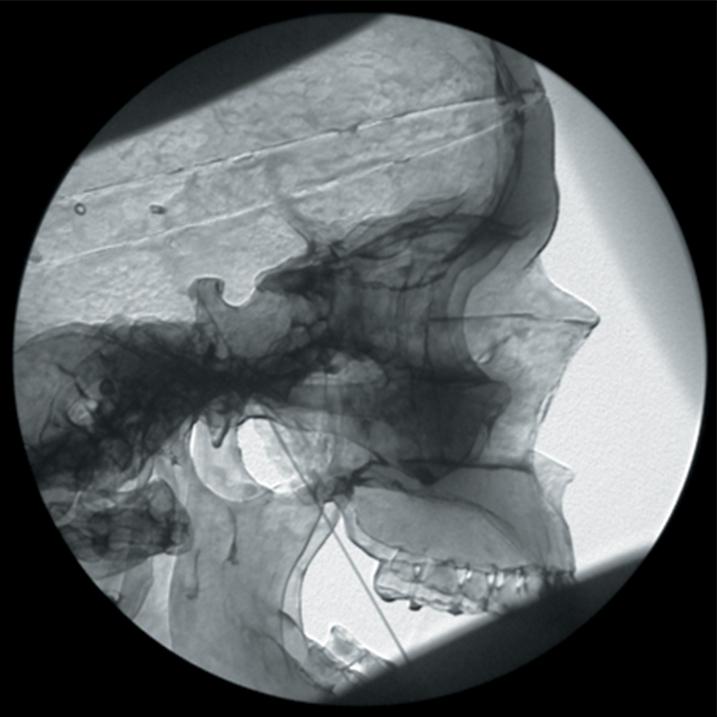

The Regional Anaesthesia Simulation Manikin has been designed by a Consultant Anaesthetist at the Manchester and Salford Pain Centre for training anaesthetists in correct needle placement in Nerve Blocks for pain management.

- Trigeminal ganglion block or radiofrequency needle placement

- The manikin consists of a specially coated plastic human skeleton, head covered in artificial skin and fabric covered torso, on which trainees can practice the placement of needles under X-ray image intensifier control

- The X-ray density of the manikin is low so that the doses of radiation used during simulated procedures are reduced